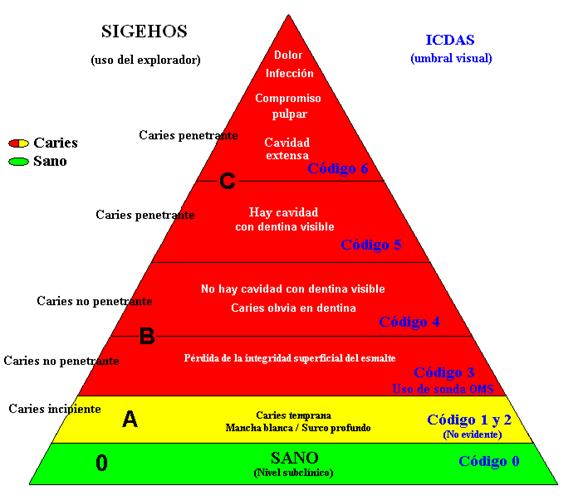

Pirámide Diagnóstica:

Criterio diagnóstico convencional de caries utilizado en

Argentina (SIGEHOS) e ICDAS |

|